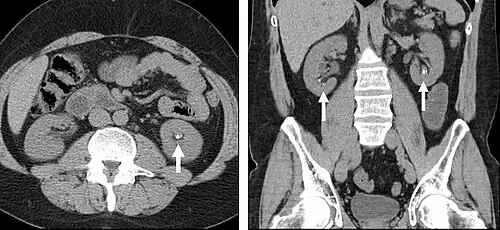

Detection and characterization of renal parenchymal masses is a frequent indication for CT. An initial noncontrast CT is important for detecting calcium or fat in a lesion, and to provide baseline attenuation of any renal masses. Following noncontrast scanning, intravenous contrast is injected and a corticomedullary phase is obtained at approximately 70 seconds (figure 7a, 7b). The corticomedullary phase is characterized by enhancement of the renal cortex as well as the renal vasculature. This phase is valuable in the evaluation of benign renal variants, lymphadenopathy and vasculature, however certain medullary renal masses may not be visible during this phase due to minimal enhancement of the medulla and collecting system. The parenchymal phase is obtained approximately 100–200 seconds after the injection of contrast material (figure 7c). Parenchymal phase imaging demonstrates continued enhancement of the cortex, enhancement of the medulla, and various levels of contrast material in the collecting system. The parenchymal phase is highly important for the detection and characterization of renal masses, parenchymal abnormalities, and the renal collecting system. This method of imaging does not evaluate for abnormalities of the collecting system.

FIGURE 7. Selected images from a renal mass specific protocol CT. Corticomedullary phase (axial 7a) demonstrates peripheral enhancement of the renal cortex with minimal opacification of the renal medulla. There is a large renal cell carcinoma in the left kidney (right in image) which can be differentiated from the normal renal parenchyma by the heterogeneous and differential enhancement. The renal artery and vein are opacified in this phase as well. The collecting system is not opacified (coronal reformat 7b). In the parenchymal phase, the renal cortex and the medulla are enhancing. The renal cell carcinoma in the left kidney is not as well defined when compared to the corticomedullary phase images, but is actually slightly more conspicuous. There is some contrast noted within the collecting system during this phase (7c).